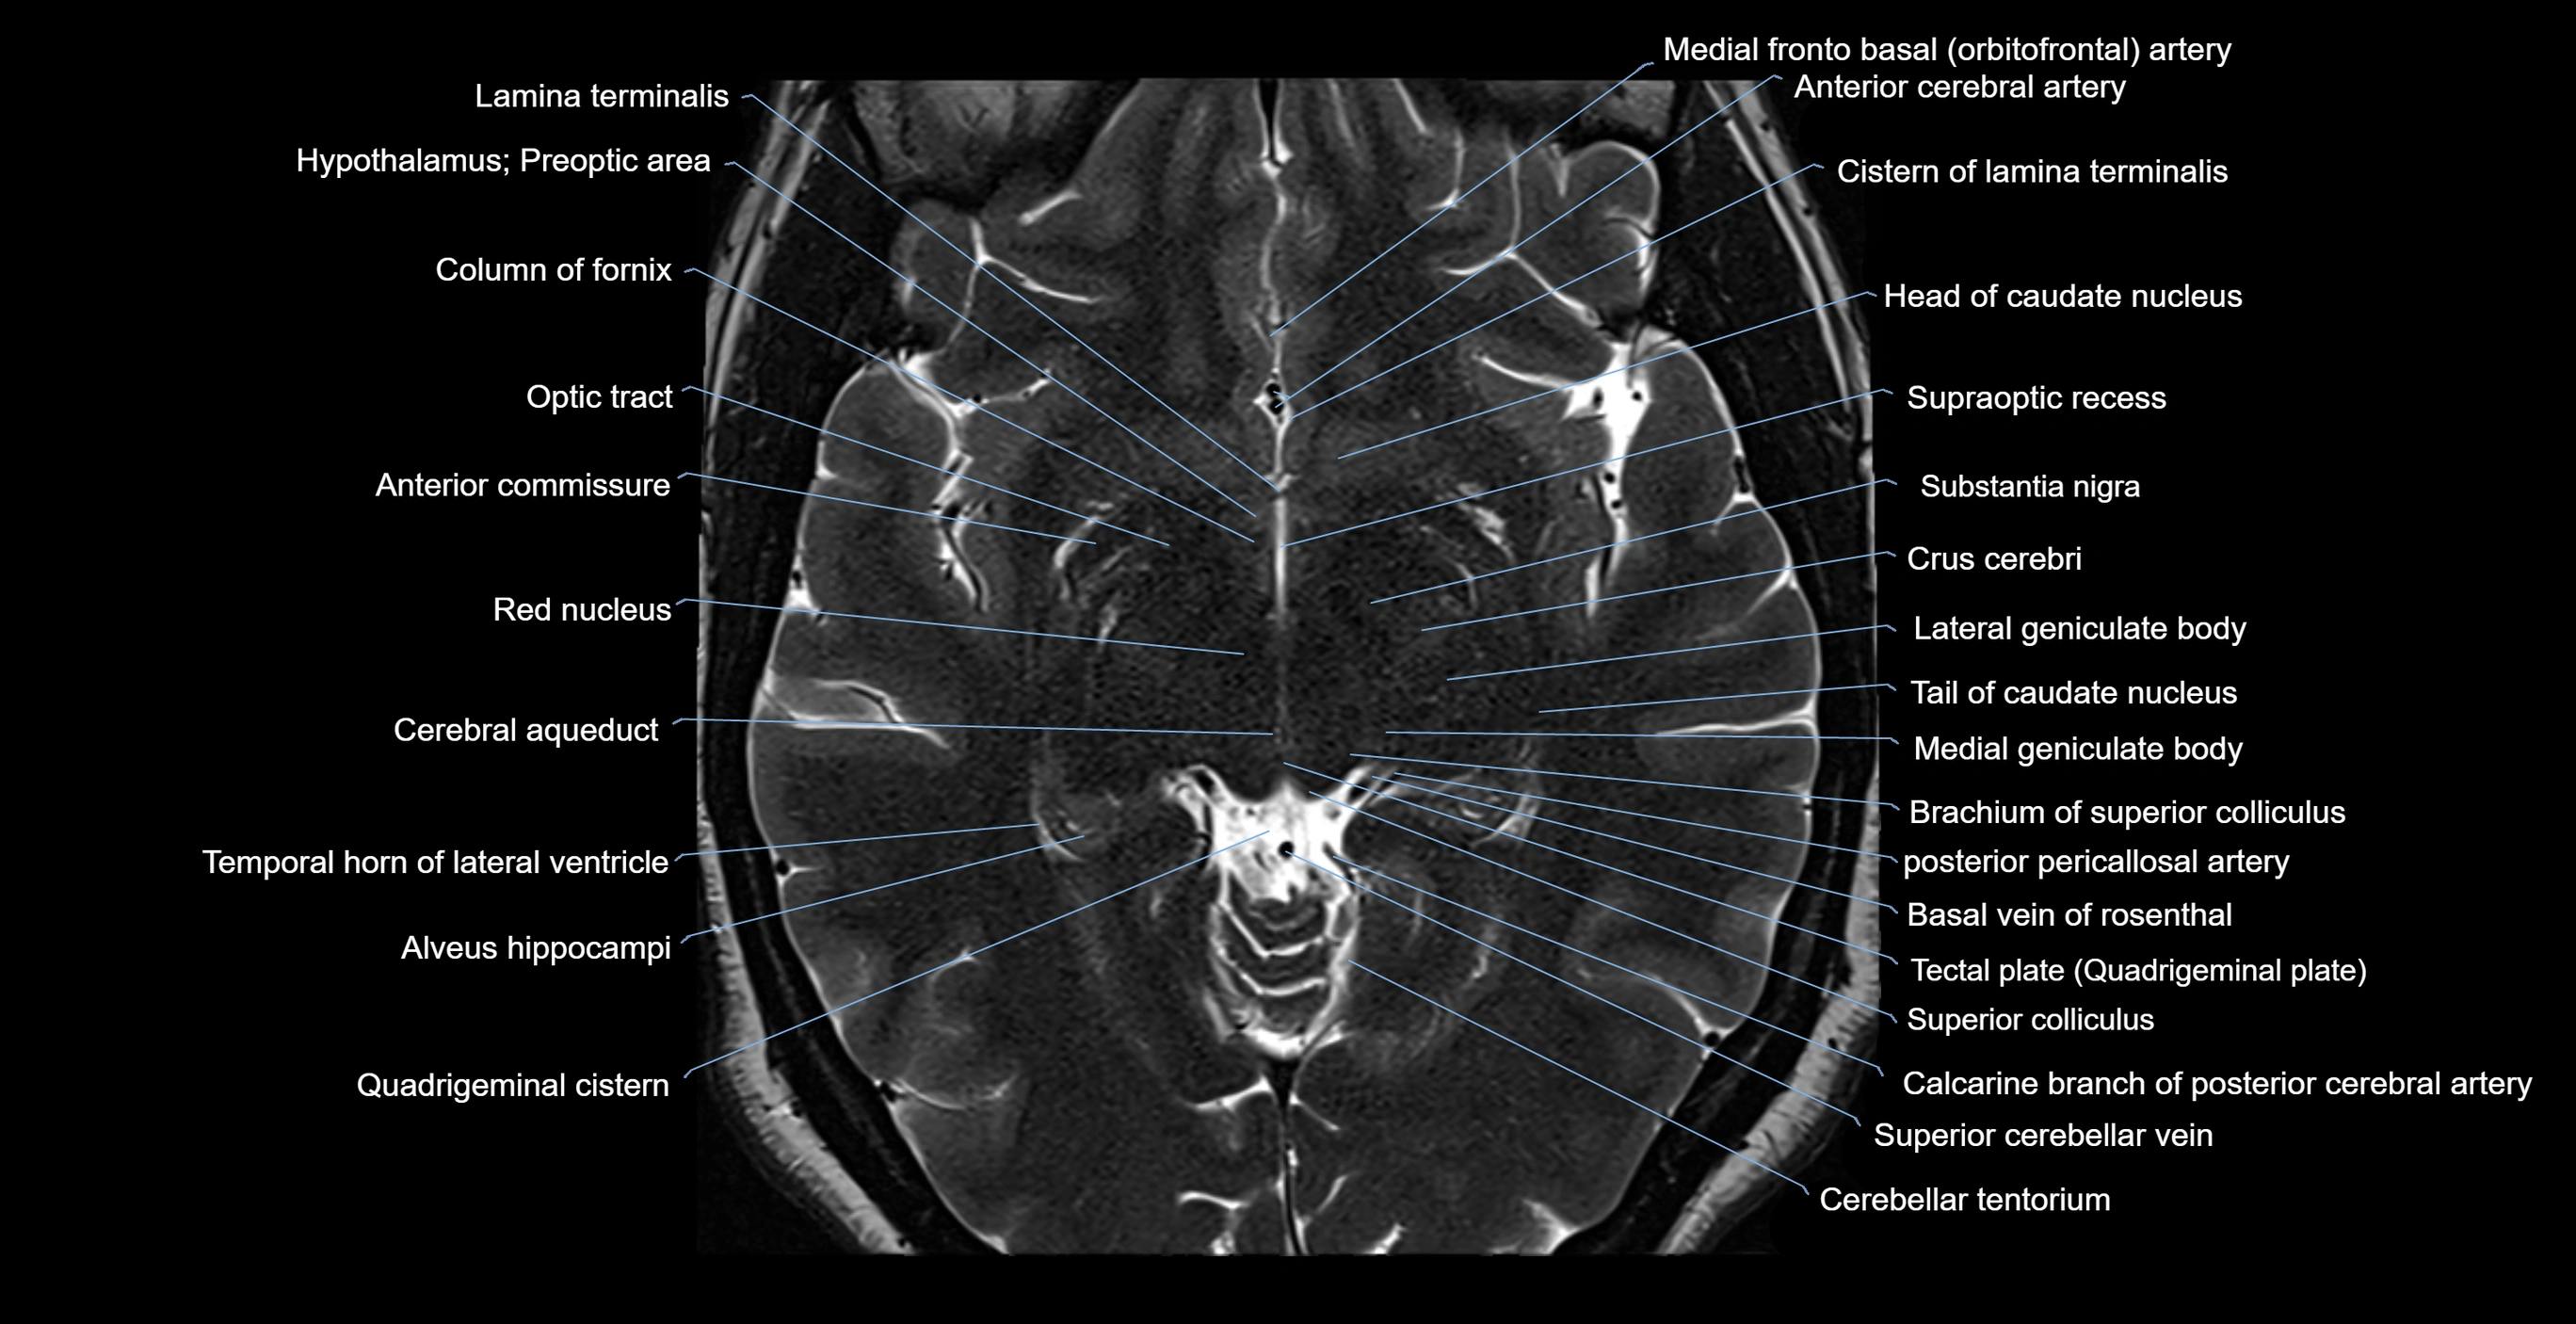

- Amygdala

- Anterior commissure

- Brachium of superior colliculus

- Cerebral aqueduct

- Column of fornix

- Crus cerebri

- Hypothalamus

- Lamina terminalis

- Lateral geniculate body

- Medial geniculate body

- Optic tract

- Pineal gland

- Quadrigeminal cistern

- Red nucleus

- Substantia nigra

- Superior colliculus

- Supraoptic recess

- Temporal horn of lateral ventricle